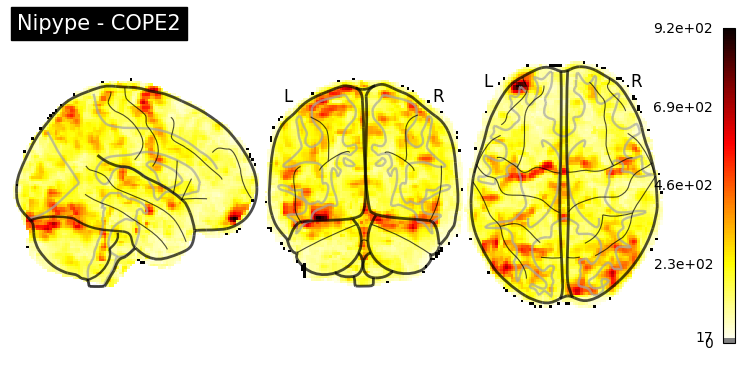

The first-level GLM#

Here we randomly choose the four copes from subject-09 run-1

nipype_cope1 = './output_level1/level1_results/09/results_dir/_subject_id_09/_level1estimate0/results/cope1.nii.gz'

nipype_cope2 = './output_level1/level1_results/09/results_dir/_subject_id_09/_level1estimate0/results/cope2.nii.gz'

nipype_cope3 = './output_level1/level1_results/09/results_dir/_subject_id_09/_level1estimate0/results/cope3.nii.gz'

nipype_cope4 = './output_level1/level1_results/09/results_dir/_subject_id_09/_level1estimate0/results/cope4.nii.gz'

plotting.plot_stat_map(nipype_cope1, bg_img=nipype_cope1, title = 'Nipype - COPE1', cmap = 'bwr', colorbar = False)

plt.show()

plotting.plot_stat_map(nipype_cope2, bg_img=nipype_cope1, title = 'Nipype - COPE2', cmap = 'bwr', colorbar = False)

plotting.plot_stat_map(nipype_cope3, bg_img=nipype_cope1, title = 'Nipype - COPE3', cmap = 'bwr', colorbar = False)

plotting.plot_stat_map(nipype_cope4, bg_img=nipype_cope1, title = 'Nipype - COPE4', cmap = 'bwr', colorbar = False)

../../_images/a7f7f387884673a96e62aa7d2d938a6b6487846759bc4500b6d0cff677c7358d.png ../../_images/bc743ce13891ebab23c9f6c7d4d668db8d11c9409d4f6e4580f7d63b35ecdb77.png ../../_images/228b3b22c00177a8ad5dc1793cbbc90dbfb495735196a4af47e73b899de0ca82.png ../../_images/babe8f68f0856f0f1608dfe550483d8ca862aae33a659d1f970a9fbe726f3bb1.png